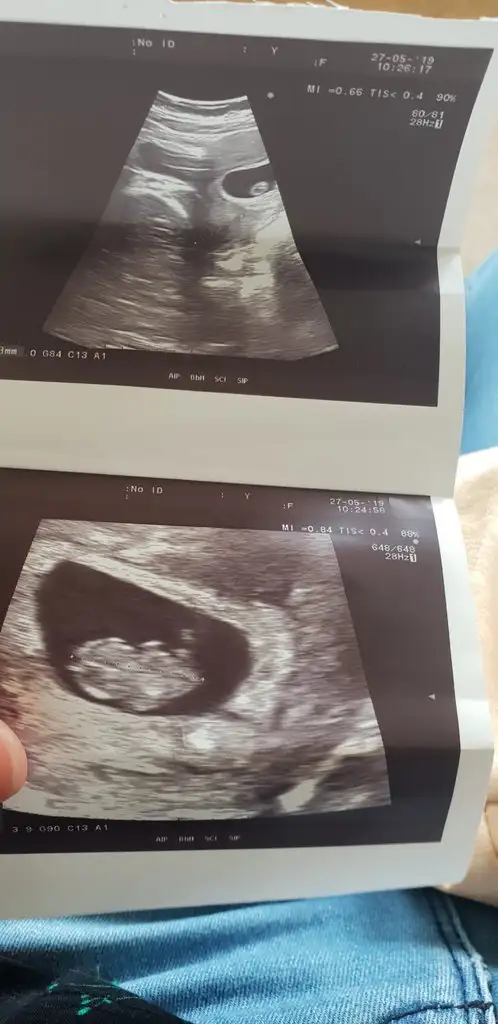

Kizlar banada yorum lutfen 1.resim 6 haftalik vajinal

2.resim 7 haftalik karindan usg

3 resimde 9 haftalik karindan yorumlarsaniz cok sevinirimmm